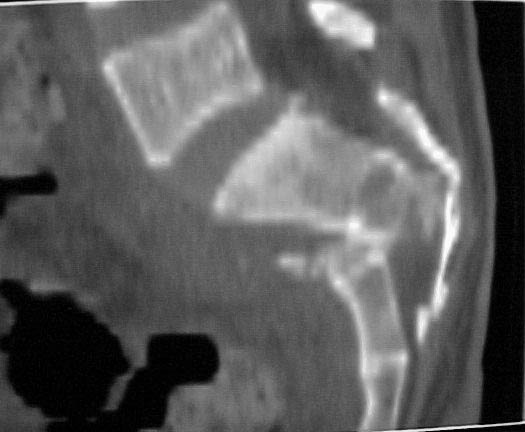

A 28 year old male jumped from the 4th floor on 11-25-2000 sustaining an L1 burst fracture that has been fixed anteriorly by the neurosurgeon with a strut between T12 and L2. A Kaneda device was placed anteriorly as well. My concern is the pelvic ring injury. There are bilateral sacral fractures through the foramen and a transverse element through the sacrum between S2 and S3. the lower part of the sacrum is displaced forward. Anteriorly there are right superior and inferior pubic rami fractures.

Sagittal

Also, please note that the caudal sacral component is not displaced anteriorly...this is the stable component of the sacral injury which remains attached to the uninvolved portion of the pelvic ring. The spinal segment is the unstable/displaced component.

Realize that the cervico-thoracic-lumbar-upper sacral segment is the unstable and displaced component.